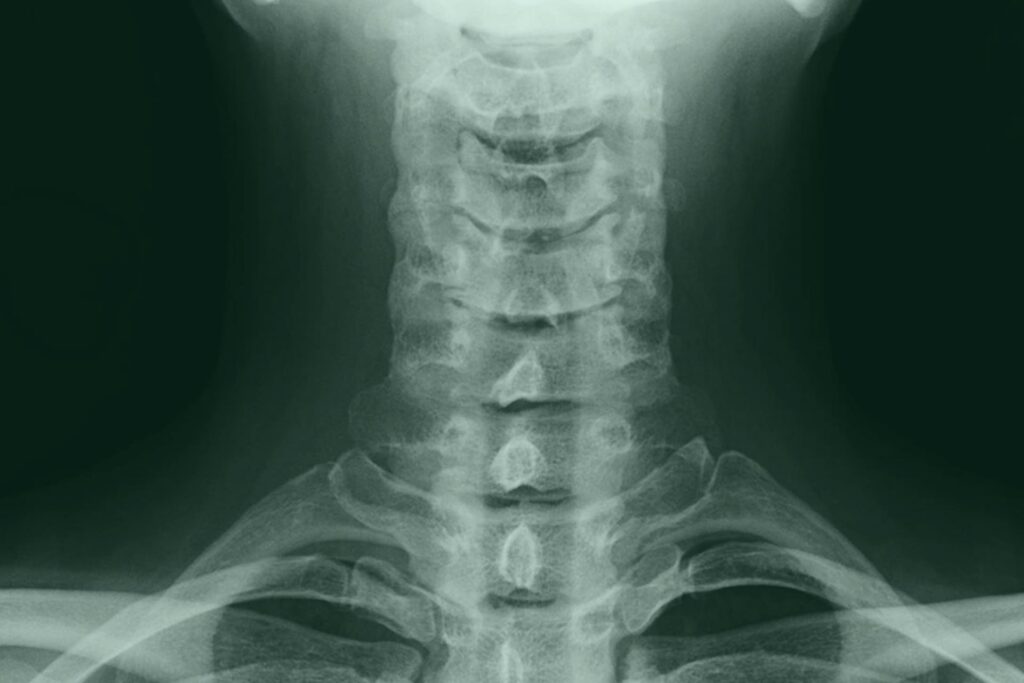

頚椎とは、椎骨の一部で、頭を支えるための骨であり、頚椎捻挫の病態については、頚部(頭(頭部)と胴体をつなぐ部位、くび)に過度の屈曲(折れ曲がること)や伸展(のび広がること)が加わった結果、頚部の靭帯や筋肉といった軟部組織が完全に断裂しない程度に損傷されたと考えられています。しかしながら、その詳細は現在の医学においても正確に解明されておらず、いまだ病態は不明な部分が多いのが実情です。

交通事故によって頸椎捻挫を負った場合、病院では基本的に以下の検査や症状の確認がなされます。

① レントゲン検査(骨折や脱臼が認められない場合)